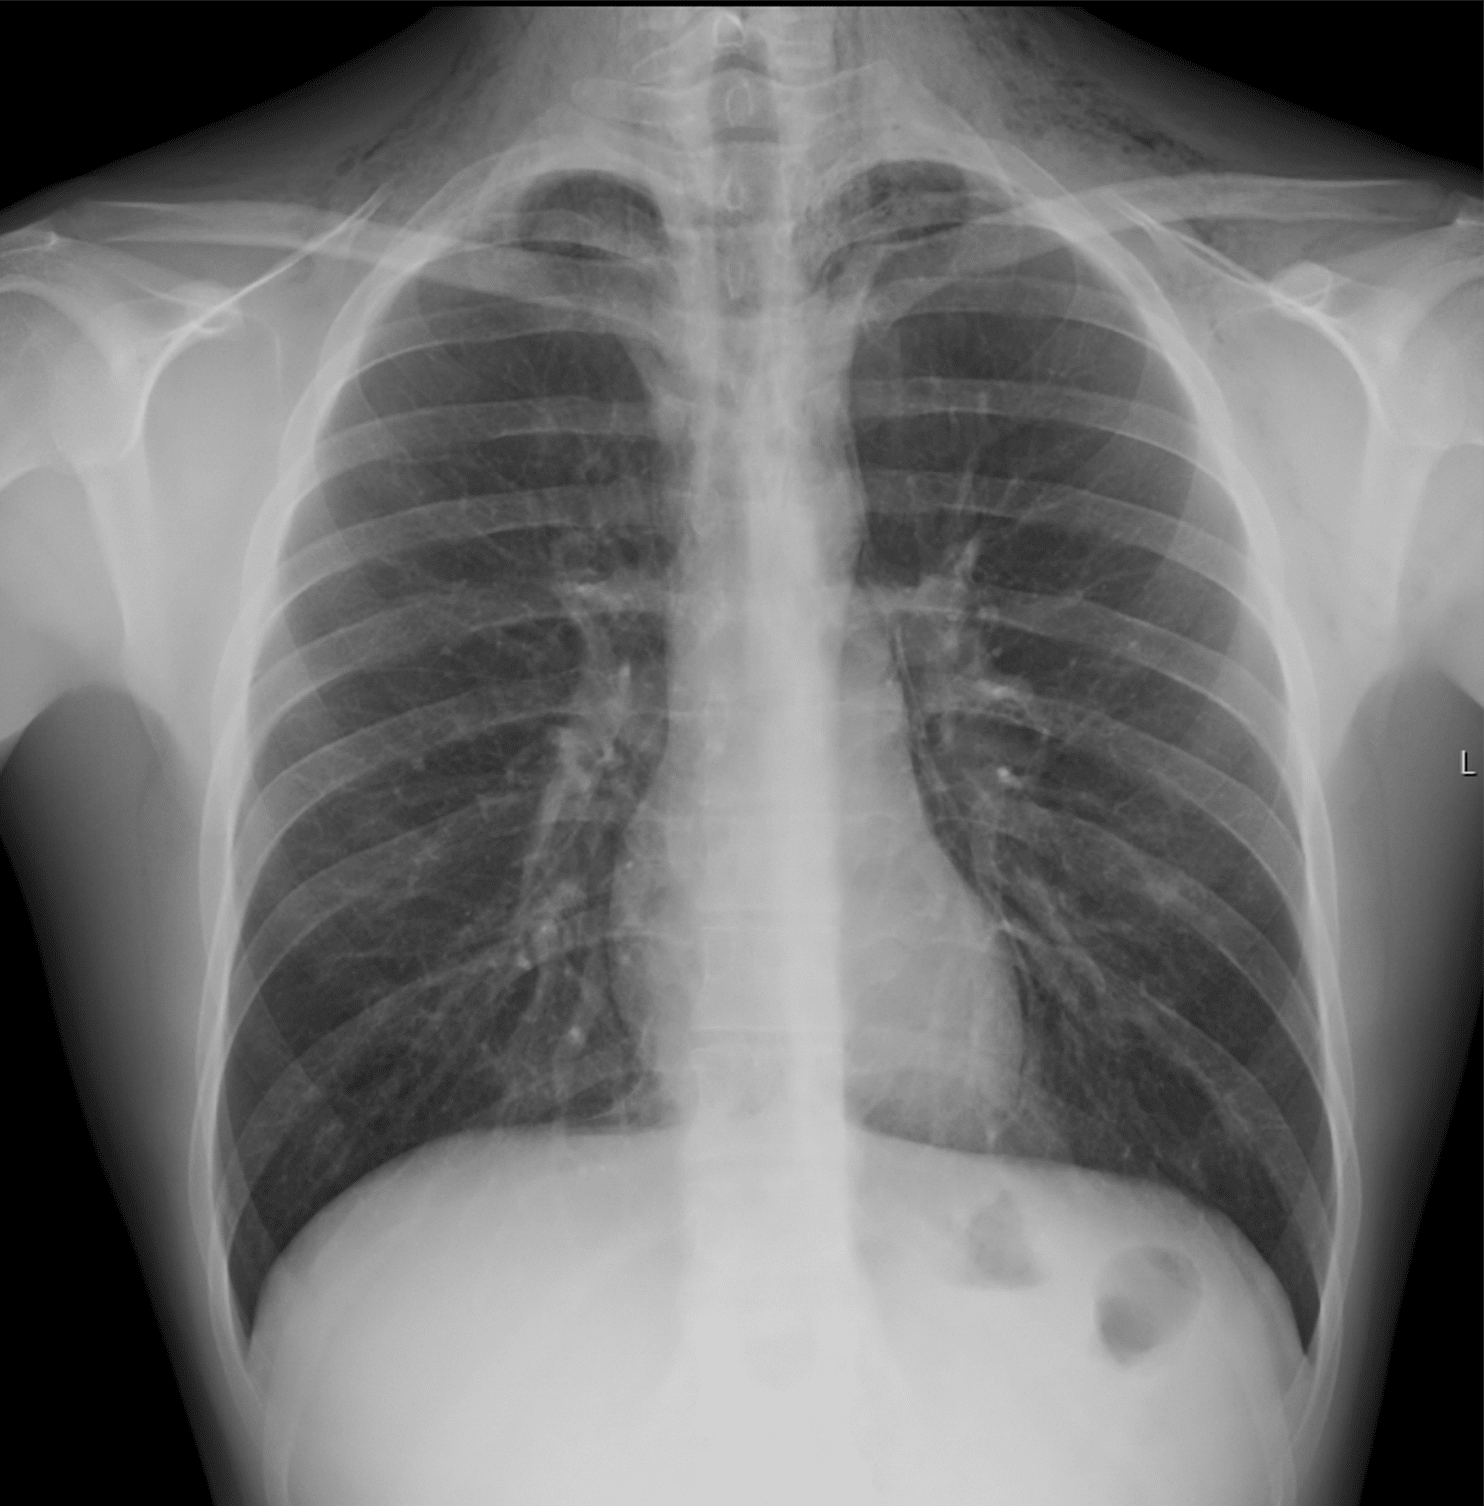

Pneumomediastinum er en sjelden, men viktig differensialdiagnose ved halshevelse og thorakale smerter. Tilstanden kan oppstå spontant eller sekundært til traume, kirurgi eller underliggende sykdom. Den vanligste patofysiologiske mekanismen er Macklins effekt, der økt intralveolært trykk fører til ruptur av alveolene og luftlekkasje langs bronkovaskulære strukturer til mediastinum (1). Spontan pneumomediastinum forekommer hyppigst hos unge voksne og forbindes med hoste, anstrengelse, oppkast eller Valsalvas [...]